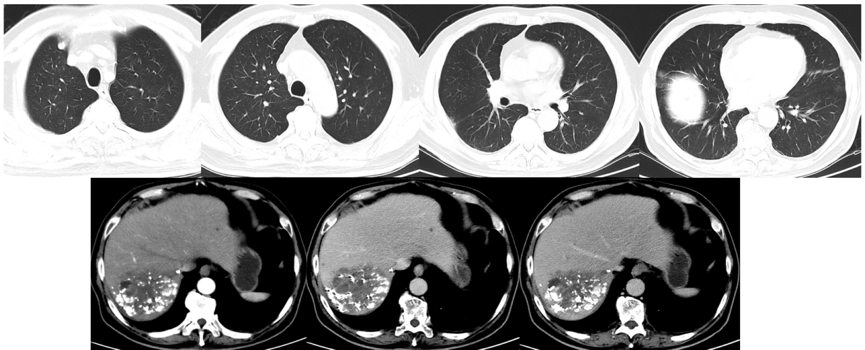

2021年4月29日、2021年6月11日、2021年7月2日、2021年8月16日和2021年9月6日复查AFP分别为242ng/ml、11.93ng/ml、16.62ng/ml、52.61ng/ml和142.1ng/ml。2021年9月7日复查CT示,肺部病灶基本消失,双侧肾上腺病灶明显缩小(图7)。

图7.2021年9月7日复查CT